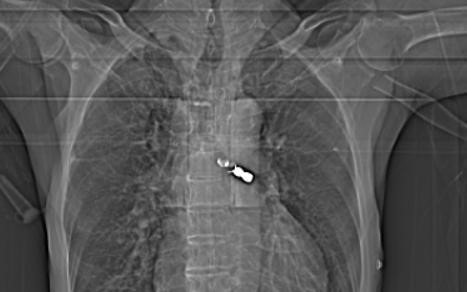

Cụ ông 92 tuổi đi làm răng, bị răng giả rơi vào phế quản

PLBĐ - Bệnh viện đa khoa tỉnh Phú Thọ thông tin, các bác sĩ Khoa Nội Hô hấp – Tiêu hóa bệnh viện vừa kịp thời cấp cứu gắp chiếc răng giả trong phế quản của bệnh nhân H. 92 tuổi do bệnh nhân nuốt phải trong quá trình làm răng.